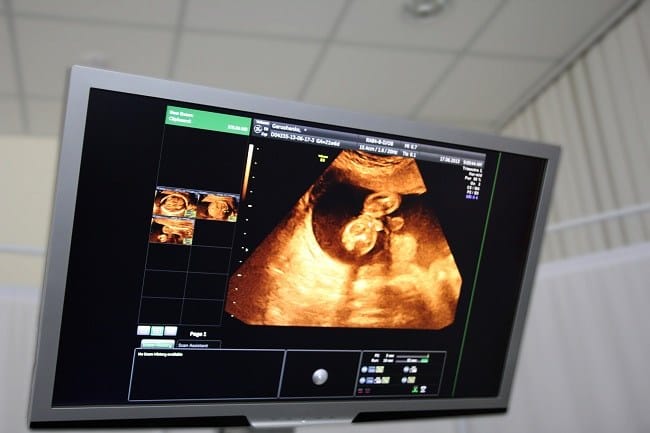

- Janin mulai bergerak dan sudah dapat dilihat melalui pemeriksaan USG